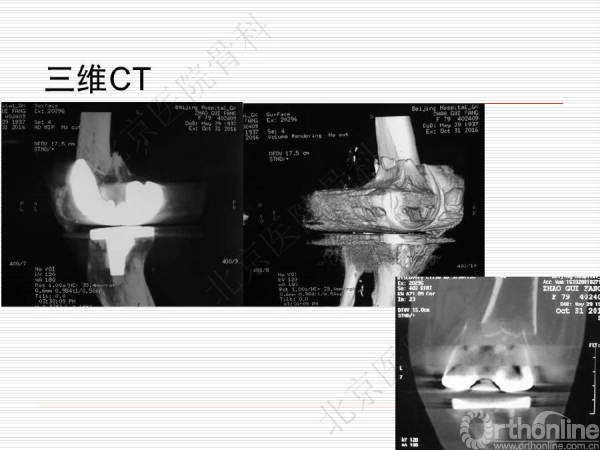

膝关节假体周围骨质疏松骨折1例

骨质疏松性骨折与创伤性骨折不同,是基于全身骨质疏松存在的一个局部骨组织病变,是骨强度下降的体现,也是骨质疏松症的最终结果。骨质疏松骨折是常见病、多发病,严重威胁中老年人身体健康,由此引起的骨质疏松性骨折,除了给患者本人造成极大的痛苦外,也给社会和家庭造成了沉重的经济和生活负担。来自北京医院骨科纪泉教授为我们带来一例经典的《膝关节假体周围骨质疏松骨折》病例,遂抗骨质疏松治疗预防再次骨折,任重而道远!